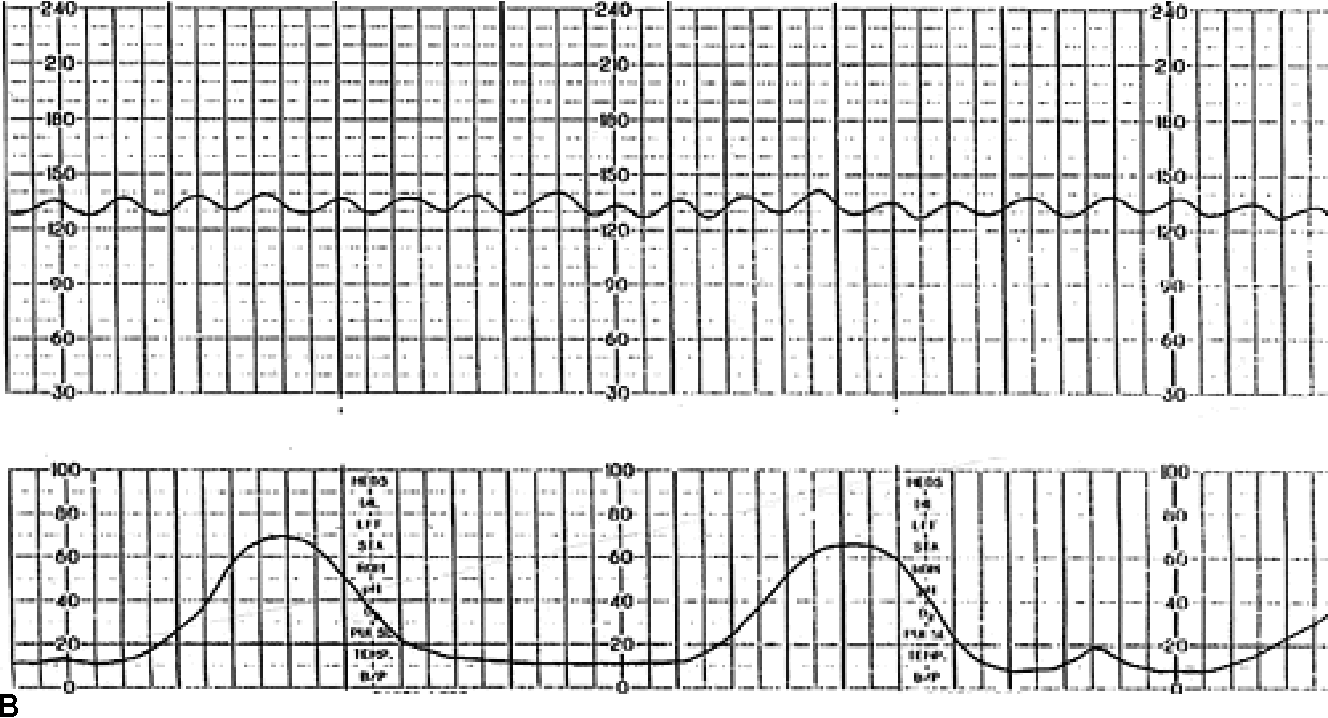

Figure 11 From Interpretation Of The Electronic Fetal Heart Rate During Labor Semantic Scholar

Figure 2 From Title Sinusoidal Heart Rate Pattern Reappraisal Of Its Definition And Clinical Significance Semantic Scholar